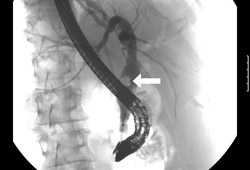

Can assist in the diagnosis of cholangitis by finding stones causing obstruction. Is also therapeutic, as the procedure can be used for biliary stone extraction. [Figure caption and citation for the preceding image starts]: Endoscopic retrograde cholangiopancreatography reveals a large common bile duct (CBD) stone (arrow) in the mid-common bile ductFrom the collection of Douglas G. Adler; used with permission [Citation ends].Endoscopic retrograde cholangiopancreatography reveals a large common bile duct (CBD) stone (arrow) in the mid-common bile duct[Figure caption and citation for the preceding image starts]: Endoscopic photo of same patient following removal of large common bile duct (CBD) stone; note copious pus draining through the ampullaFrom the collection of Douglas G. Adler; used with permission [Citation ends].Endoscopic photo of same patient following removal of large common bile duct (CBD) stone; note copious pus draining through the ampulla

direct observation of bile duct stone or other obstruction